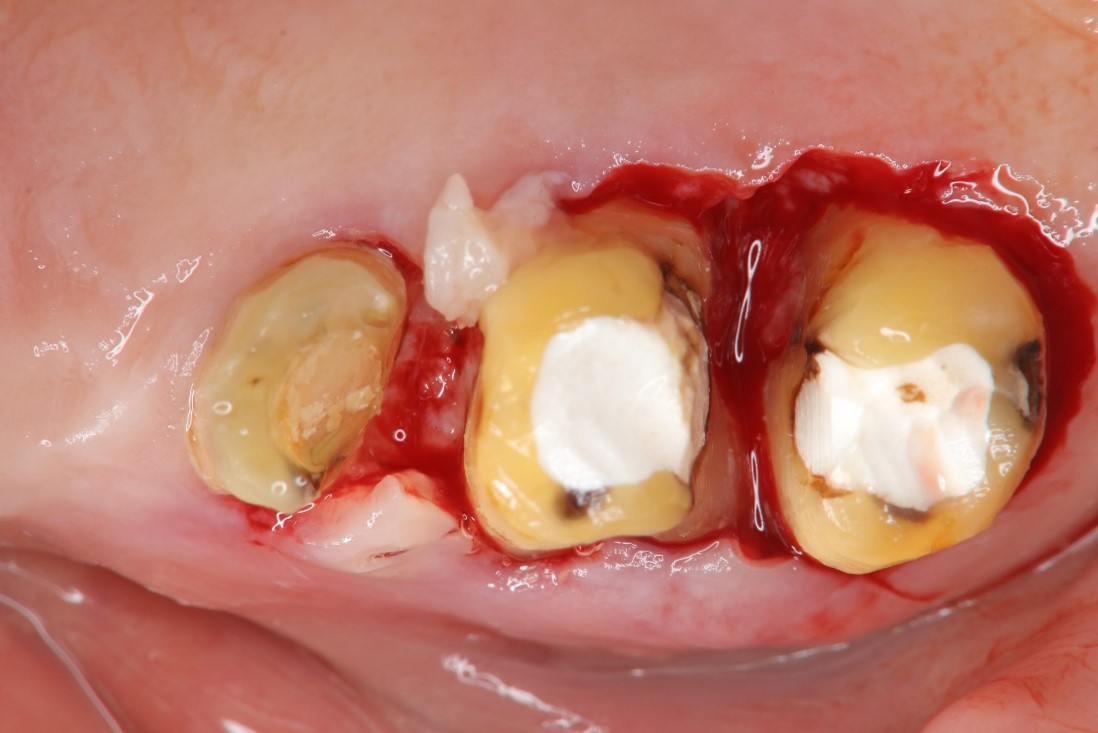

牙冠增長手術